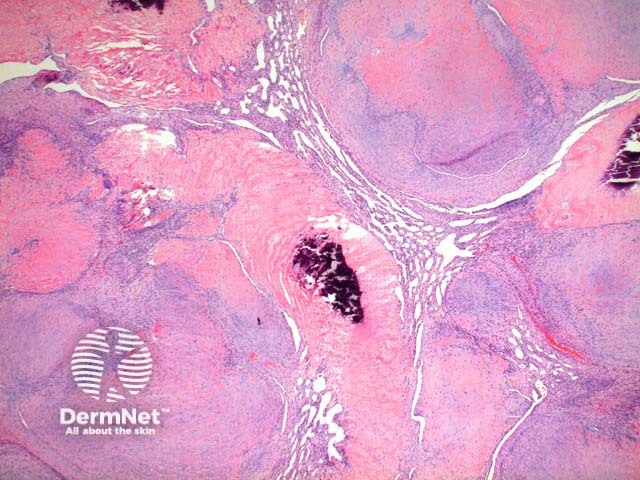

Low power view of myofibroma demonstrates a well defined multinodular tumour arising in the deep dermis or subcutis (Figure 1). Also at low power a branching ‘staghorn’ like pattern of blood vessels can be seen between the tumour nodules (Figure 2). Areas of calcification can often be seen (Figures 2, 3 and 5). The tumour nodules are comprised of a spindle cell proliferation with short plump nuclei (Figures 4,5 and 6). A basophilic tinge in the spindled peripheral component of the nodules is evident (Figures 7 and 8). Sclerotic collagen in the centre of the tumour nodules gives a biphasic appearance to the tumour (Figure 9).